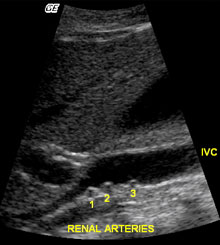

Variantele anatomice sunt relativ frecvente la nivelul vaselor renale. Aproximativ 30% din indivizi au mai mult de o artera renala. Arterele supranumerare pot aparea bilateral sau unilateral. Cele mai multe artere renale accesorii au origine in aorta abdominala, dar se pot desprinde si din arterele iliaca comuna, mezenterica superioara, mezenterica inferioara, suprarenala sau hepatica dreapta. Ramificarea precoce a arterei renale apare in aproximativ 15% din cazuri.

Figura 4 - Imagine sagitala in nuante de gri si imagine coronala color la doi pacienti cu artere supranumerare drepte. Pentru identificarea arterelor renale multiple, este utila obtinerea unei imagini a VCI in axul sau lung. O examinare atenta dedesubtul VCI evidentiaza doua artere renale drepte (A) si trei artere renale drepte (C). O alta imagine utila pentru a demonstra existenta arterelor renale supranumerare este o imagine coronara a aortei. Aceasta vedere asigura un unghi excelent pentru identificarea originii arterelor renale drepte si stangi folosind Doppler color. Figura B arata doua artere renale drepte si una stanga folosind power Doppler. Cum power Doppler nu arata directia fluxului, vena renala stanga are aceeasi culoare cu artera si poate fi usor luata drept o a doua artera renala stanga. O examinare atenta arata totusi ca vasul nu are origine in aorta, ci trece anterior de ea. Power Doppler a fost folosit si in cazul figurii D pentru a demonstra prezenta a 3 artere renale drepte si una stanga. |